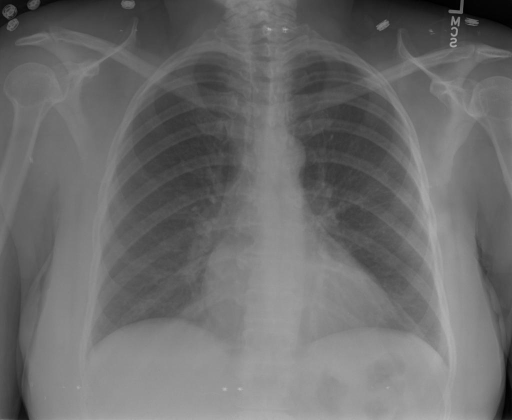

|X光影像|诊疗报告(医生)|XrayGLM|

|:-|:-|:-|

||X光图片显示没有扭曲的区域、可疑的骨质不透明度或胸腺积液。心脏大小轻微增大,但非常稳定。此外,没有气胸的证据,肺野也正常。总体来说,X光片显示没有急性心脏异常,但要注意轻微的心脏扩大。|X光片显示,心脏大小正常。肺部和纵隔轮廓清晰,没有气胸或胸腔积液的证据。骨骼结构完整,没有任何急性异常。|